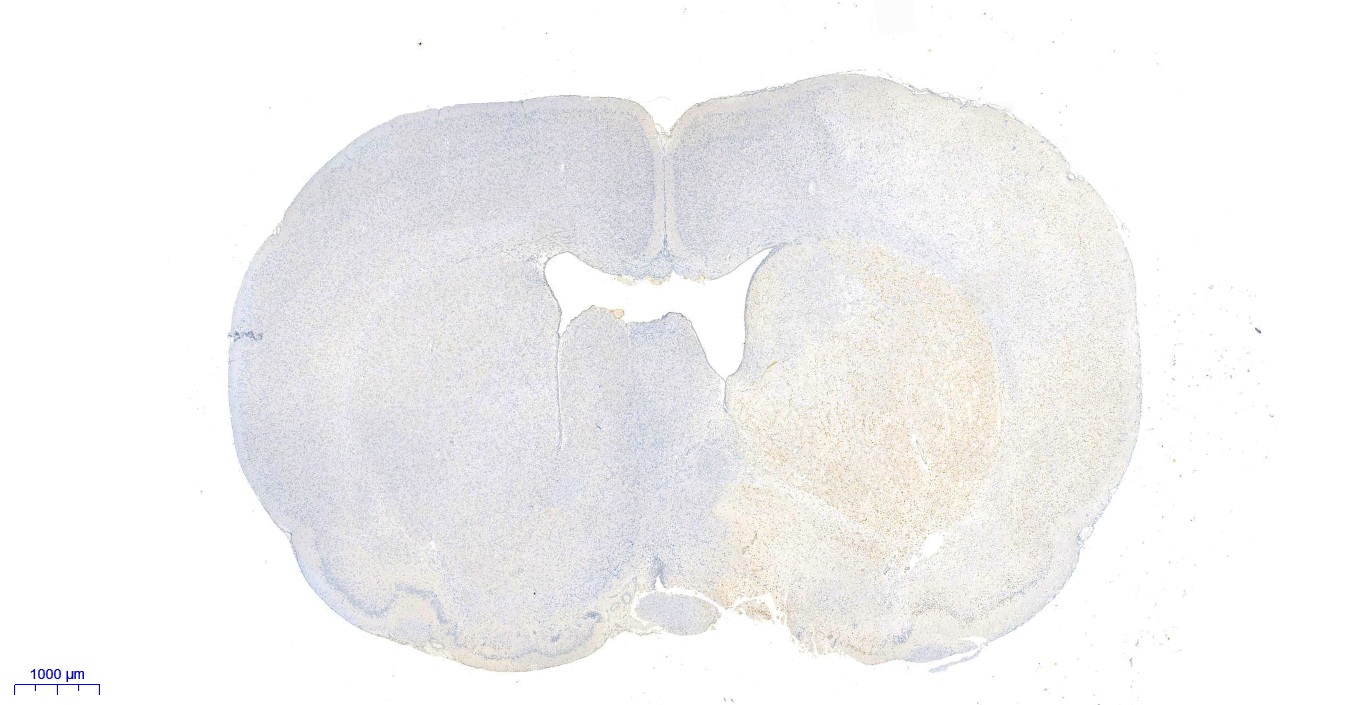

细胞凋亡中染色体DNA的断裂是个渐进的阶段性过程。染色体DNA首先在内源性的核酸水解酶的作用下降解为50-300 kb的大片段,然后大约30%的染色体DNA在Ca2+和Mg2+依赖的核酸内切酶作用下,在核小体单位之间被随机切断,形成180-200 bp核小体DNA多聚体。因此在细胞凋亡晚期,DNA会被降解为180-200 bp的片段,断裂的基因组DNA上暴露出大量的3'-OH末端。末端脱氧核糖核苷酸转移酶(Terminal Deoxynucleotidyl Transferase, TdT)是一种不依赖于模板的DNA聚合酶,可以催化脱氧核苷酸结合到断裂的DNA分子3'-OH末端。因此TUNEL (TdT mediated dUTP Nick End Labeling)细胞凋亡检测试剂盒可以用来检测组织细胞在凋亡晚期过程中细胞核DNA的断裂情况。其原理是在TdT酶的作用下,在基因组DNA断裂时暴露出的3´-OH末端掺入生物素标记的dUTP(Biotin-dUTP),随后用辣根过氧化物酶(Horse-radish peroxidase,HRP)标记的链霉亲和素(Streptavidin)(Streptavidin-HRP, SA-HRP),检测被生物素(Biotin)标记的DNA末端,最后通过加入HRP的底物混合液(DAB)进行显色反应,使得凋亡细胞的细胞核被染成棕黄色,从而可以用普通光学显微镜检测。本试剂盒应用范围广,适用于石蜡组织切片,冰冻组织切片、细胞爬片、细胞涂片等的细胞凋亡检测。

13. 镜检:样本使用白光显微镜进行镜检(发生凋亡的阳性细胞核被染成棕黄色,正常的阴性细胞核被染成蓝色)。